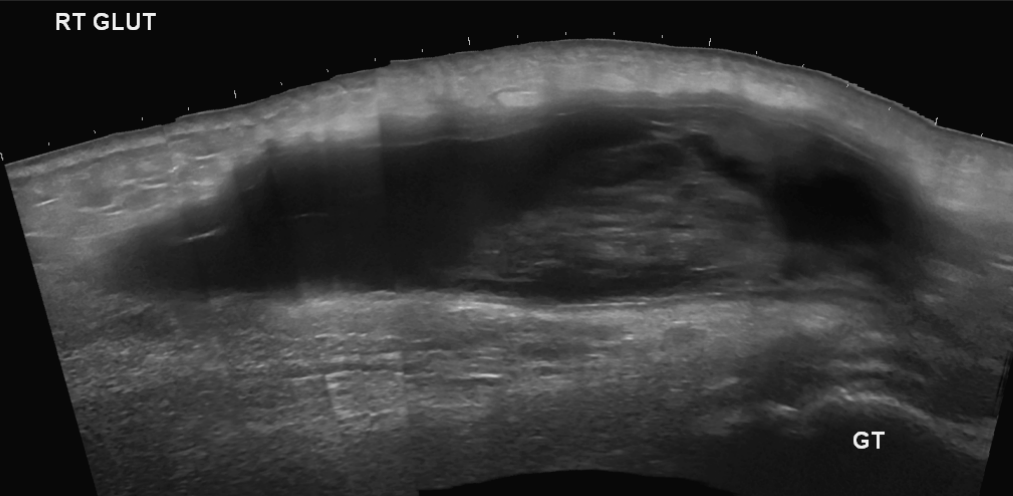

Gluteal haematoma